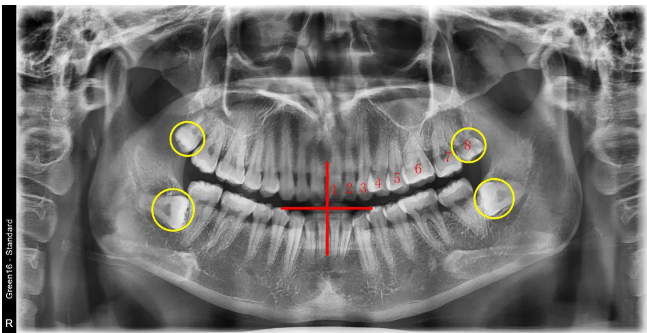

🔎埋伏牙

🔎儿童恒牙萌出

🔎牙齿不齐

🔎根尖炎症